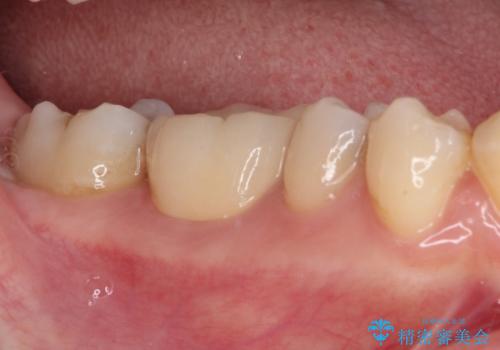

放置した虫歯 根管治療とオールセラミッククラウン

- 奥歯の虫歯を放置してしまい、痛みを感じることがあるとのことで来院された患者様です。

術前の診査では、神経を取り除かなくても済む可能性が示唆されましたが、実際に虫歯除去を進めたところ、レントゲン写真から読み取れる通り、神経組織にまで虫歯が及んでいることが分かりました。

速やかにラバーダム下にて根管治療を行うこととし、その後オールセラミッククラウンにて補綴治療を行うこととしました。

治療期間中、痛みが生じることはなく、処置後3か月経過しましたが良好な状態を保っています。